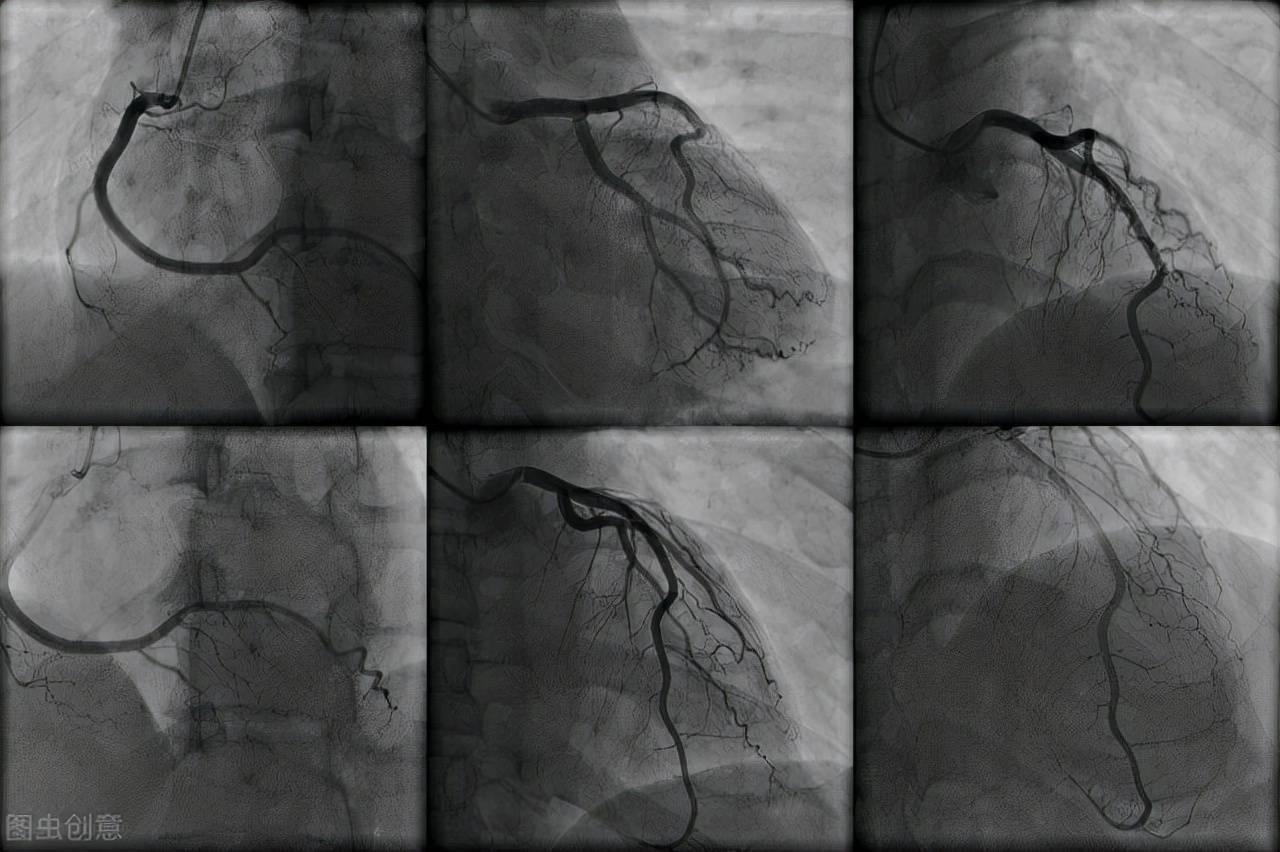

医生解释了_心脑血管_患者_造影

图片尺寸1280x852